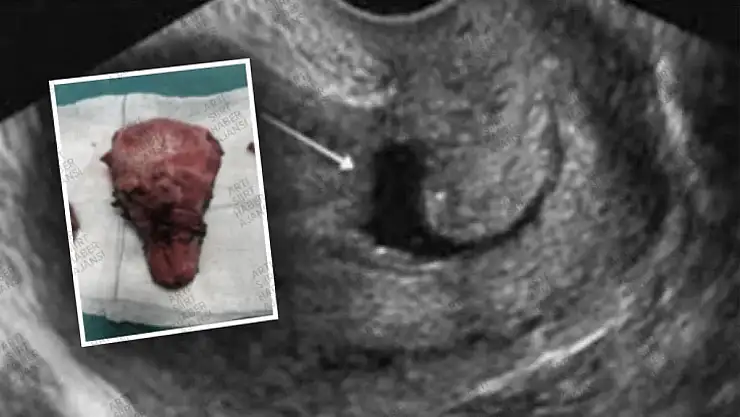

Kurtalan Devlet Hastanesi'ne başvuran 42 yaşındaki bir kadın hasta, vajinal kanama, tansiyon düşüklüğü ve baş dönmesi şikayetleriyle acil servise geldi. İlk müdahaleyi yapan Op. Dr. Fırat Onursal, hastanın geçmiş tıbbi öyküsünü değerlendirerek eski sezaryen kesi yerinde oluşmuş istmosel adı verilen bir yapının kanamaya neden olduğunu belirledi. Bu durum, sezaryen sonrası rahim kas dokusunun tam olarak iyileşememesi sonucu rahim iç duvarında bir kese oluşmasıyla kendini gösterir.

Hastanın daha ileri tetkik ve tedavi için Siirt Eğitim ve Araştırma Hastanesi'ne sevk edilmesine karar verildi. Burada, Op. Dr. Fatma Zehra Kurnuç ve Op. Dr. Fırat Onursal tarafından kapalı yöntemle (laparoskopik) ameliyat gerçekleştirildi. Ameliyat sırasında, kanamaya neden olan istmosel yapısı başarılı bir şekilde onarıldı. Hastanın ameliyat sonrası durumu iyiye gitti ve kısa sürede taburcu edildi.

Uzman doktorlar, istmosel durumunun potansiyel komplikasyonları konusunda uyarıda bulundu. Sezaryen ameliyatı sonrasında oluşabilecek bu yapının, akut kanama, adet düzensizlikleri, regl bitiminde çamur renginde kanamalar ve tekrarlayan vajinal enfeksiyonlara yol açabileceği vurgulandı. İsthmosel ayrıca, ilişki sırasında ağrıya ve olası gebelik durumunda embriyonun bu keseye yerleşmesi sonucu skar gebelik riskine de neden olabilir. Bu tür belirtiler yaşayan kadınların vakit kaybetmeden bir uzman doktora başvurması gerektiği ifade edildi.